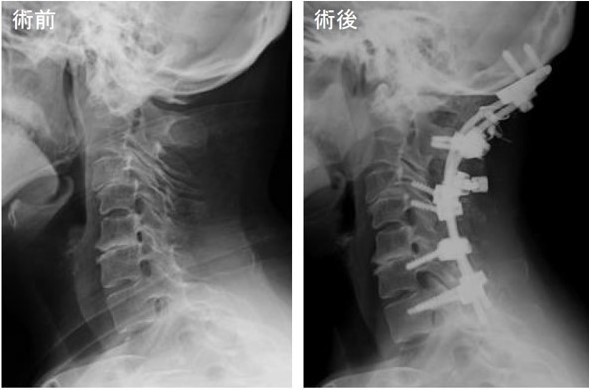

神経の圧迫を解除する除圧手術から、関節のずれを矯正・整復、さらには強固に固定する手術があり病態に応じて選択します。

後頭頚椎固定術